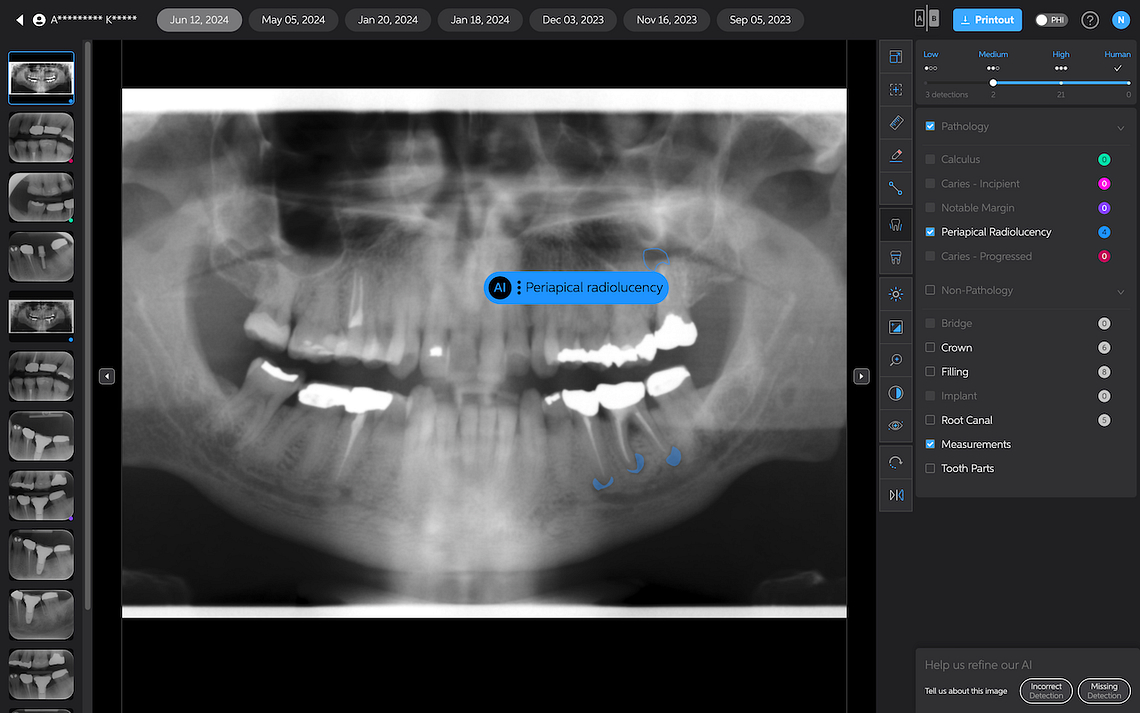

Periapical Radiolucencies

These are self-explanatory. They are outlined in blue on periapical radiographs. While this could help draw attention to potential issues, interpreting these findings would still rely heavily on the dentist's expertise.

Pearl currently only analyzes 2D radiographs, including intraoral radiographs and OPGs. 3D X-ray analysis is under development and is scheduled for release later in 2025.